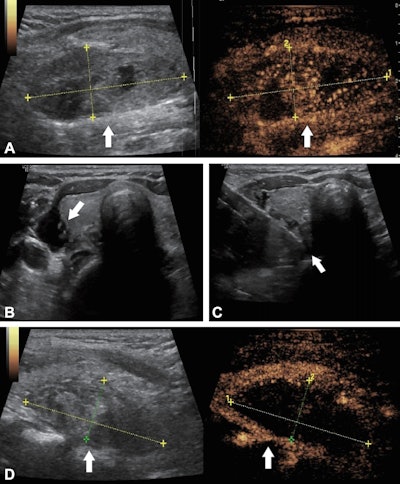

Ultrasound images in a 56-year-old woman with primary hyperparathyroidism treated using ultrasound-guided microwave ablation. (A) Preablation longitudinal images reveal a hypoechoic parathyroid nodule (arrow) measuring 4.84 × 1.86 × 2.53 cm. The B-mode image (left) shows the nodule, while the contrast-enhanced image (right) demonstrates hyperenhancement of the solid component of the parathyroid lesion. The coordinate axes indicate the measured maximum diameters of the nodule. (B) Transverse image shows percutaneous injection of saline solution (arrow) with ultrasound guidance, to create an isolation zone to protect surrounding tissues. (C) Transverse image shows the ablation needle (arrow) positioned within the nodule for microwave ablation. (D) Postablation longitudinal images of the lesion area (arrow). The B-mode image (left) shows the hyperechoic lesion area, while the contrast-enhanced image (right) shows no contrast enhancement, indicating complete ablation. The coordinate axes indicate the maximum diameters of the ablation zone (4.51 × 1.85 × 2.04 cm).RSNAAccording to the findings, 80% (61 of 76) of participants with PHPT were cured, with similar rates observed between MWA (78% [42 of 54]) and RFA (86% [19 of 22]; p = 0.59). In participants with SHPT, the parathyroid hormone (PTH) achievement rate (proportion maintaining target PTH for ≥6 months) was 90% (69 of 77), with similar rates observed between MWA (92% [36 of 39]) and RFA (87% [33 of 38]; p = 0.48), the researchers reported.